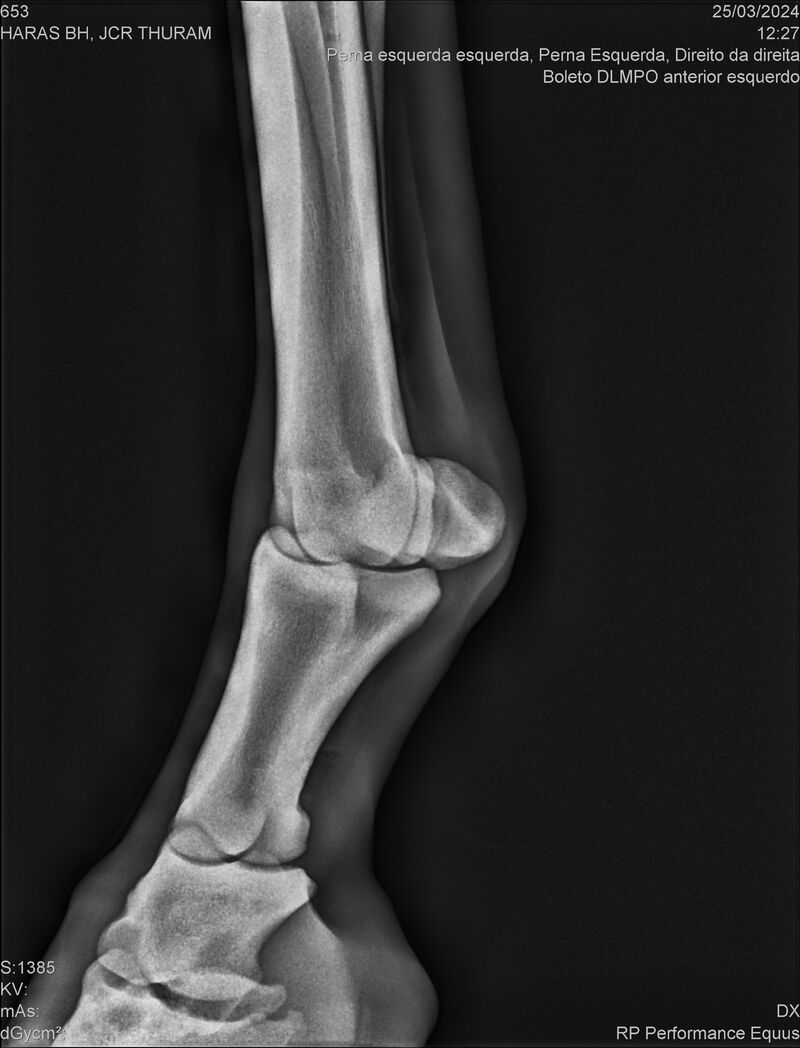

JCR THURAM

Raça: BRASILEIRO DE HIPISMO

Sexo: CASTRADO - CASTRADO

Nascimento: 10/01/2021

Registro: 27531-BH

Vend.: HARAS BH